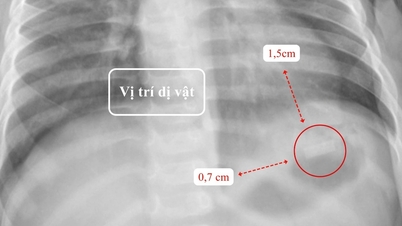

„Zur Bestätigung der Diagnose muss der FGF23-Index im Blut quantifiziert werden. In Vietnam gibt es derzeit jedoch keinen solchen Test. Daher ordneten wir bei dem Patienten eine Ganzkörper-PET/CT-Untersuchung mit radioaktiven Substanzen in Kombination mit MRT und Ultraschall an und fanden schließlich einen 1–2 cm großen Tumor im Weichteilgewebe unter dem rechten Oberschenkel“, sagte Doktor Van.

Bild eines Tumors im Weichteilbereich unter dem rechten Oberschenkel auf einer MRT-Aufnahme (Foto: BVCC).